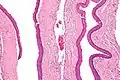

| Micrograph of an odontogenic keratocyst. H&E stain. | |

Odontogenic keratocysts have a diagnostic histological appearance. Under the microscope, OKCs vaguely resemble keratinized squamous epithelium;[14] however, they lack rete ridges and often have an artifactual separation from their basement membrane.[2]

The fibrous wall of the cyst is usually thin and uninflamed. The epithelial lining is thin with even thickness and parakeratinised with columnar cells in the basal layer which have focal reverse polarisation (nuclei are on the opposite pole of the cell).[12] The basal cells are an indication of the odontogenic origin as they resemble pre-ameloblasts. The epithelium can separate from the wall, resulting in islands of epithelium. These can go on to form 'satellite' or 'daughter' cysts, leading to an overall multilocular cyst.[9] Presence of daughter cysts is particularly seen in those with NBCCS.[12] Inflamed cysts show hyperplastic epithelium which is no longer characteristic of OKCs and can have resemblance to radicular cysts instead. Due to areas of focal inflammation, a larger biopsy is required for correct diagnosis of odontogenic keratocysts.[9]